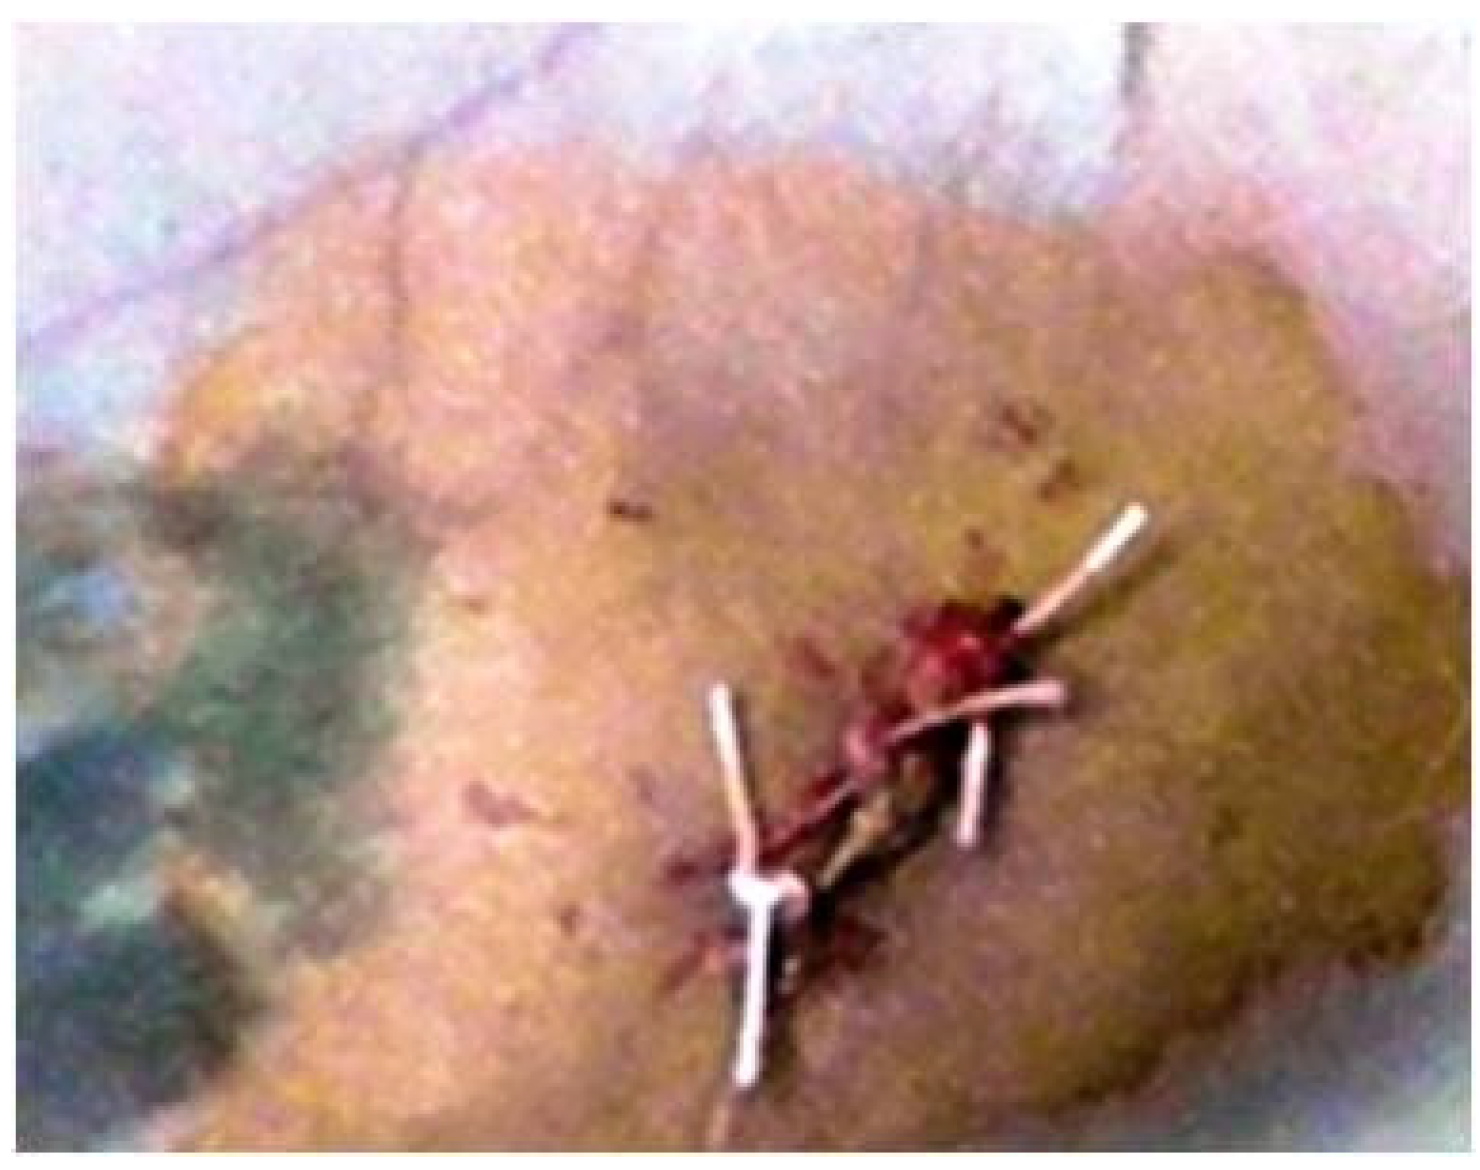

Skin incisions were made for implanting the tubes (Figure 1).

Tubes were inserted as deep as the created tissue pocket allowed. In the end, the surgical wound was sutured with non-absorbable suture thread (Figure 2).

Figure 1. Subcutaneous technique for implantation of biomaterials.